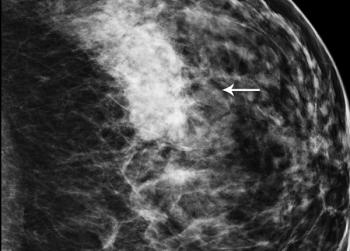

A 46-year-old patient presents for routine screening mammography. Family history of breast cancer consists of a maternal aunt and grandmother.